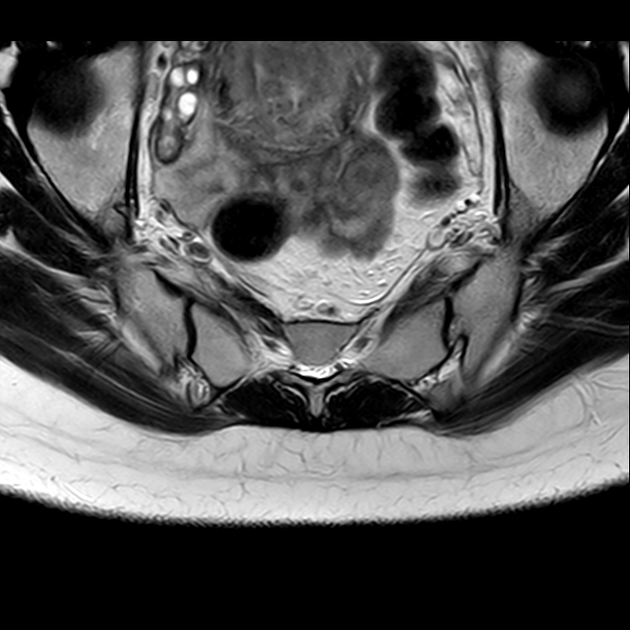

磁共振检查:

T2

6、磁共振上可以发现骨折线周边明显的骨髓水肿,增强扫描明显强化

磁共振影像表现